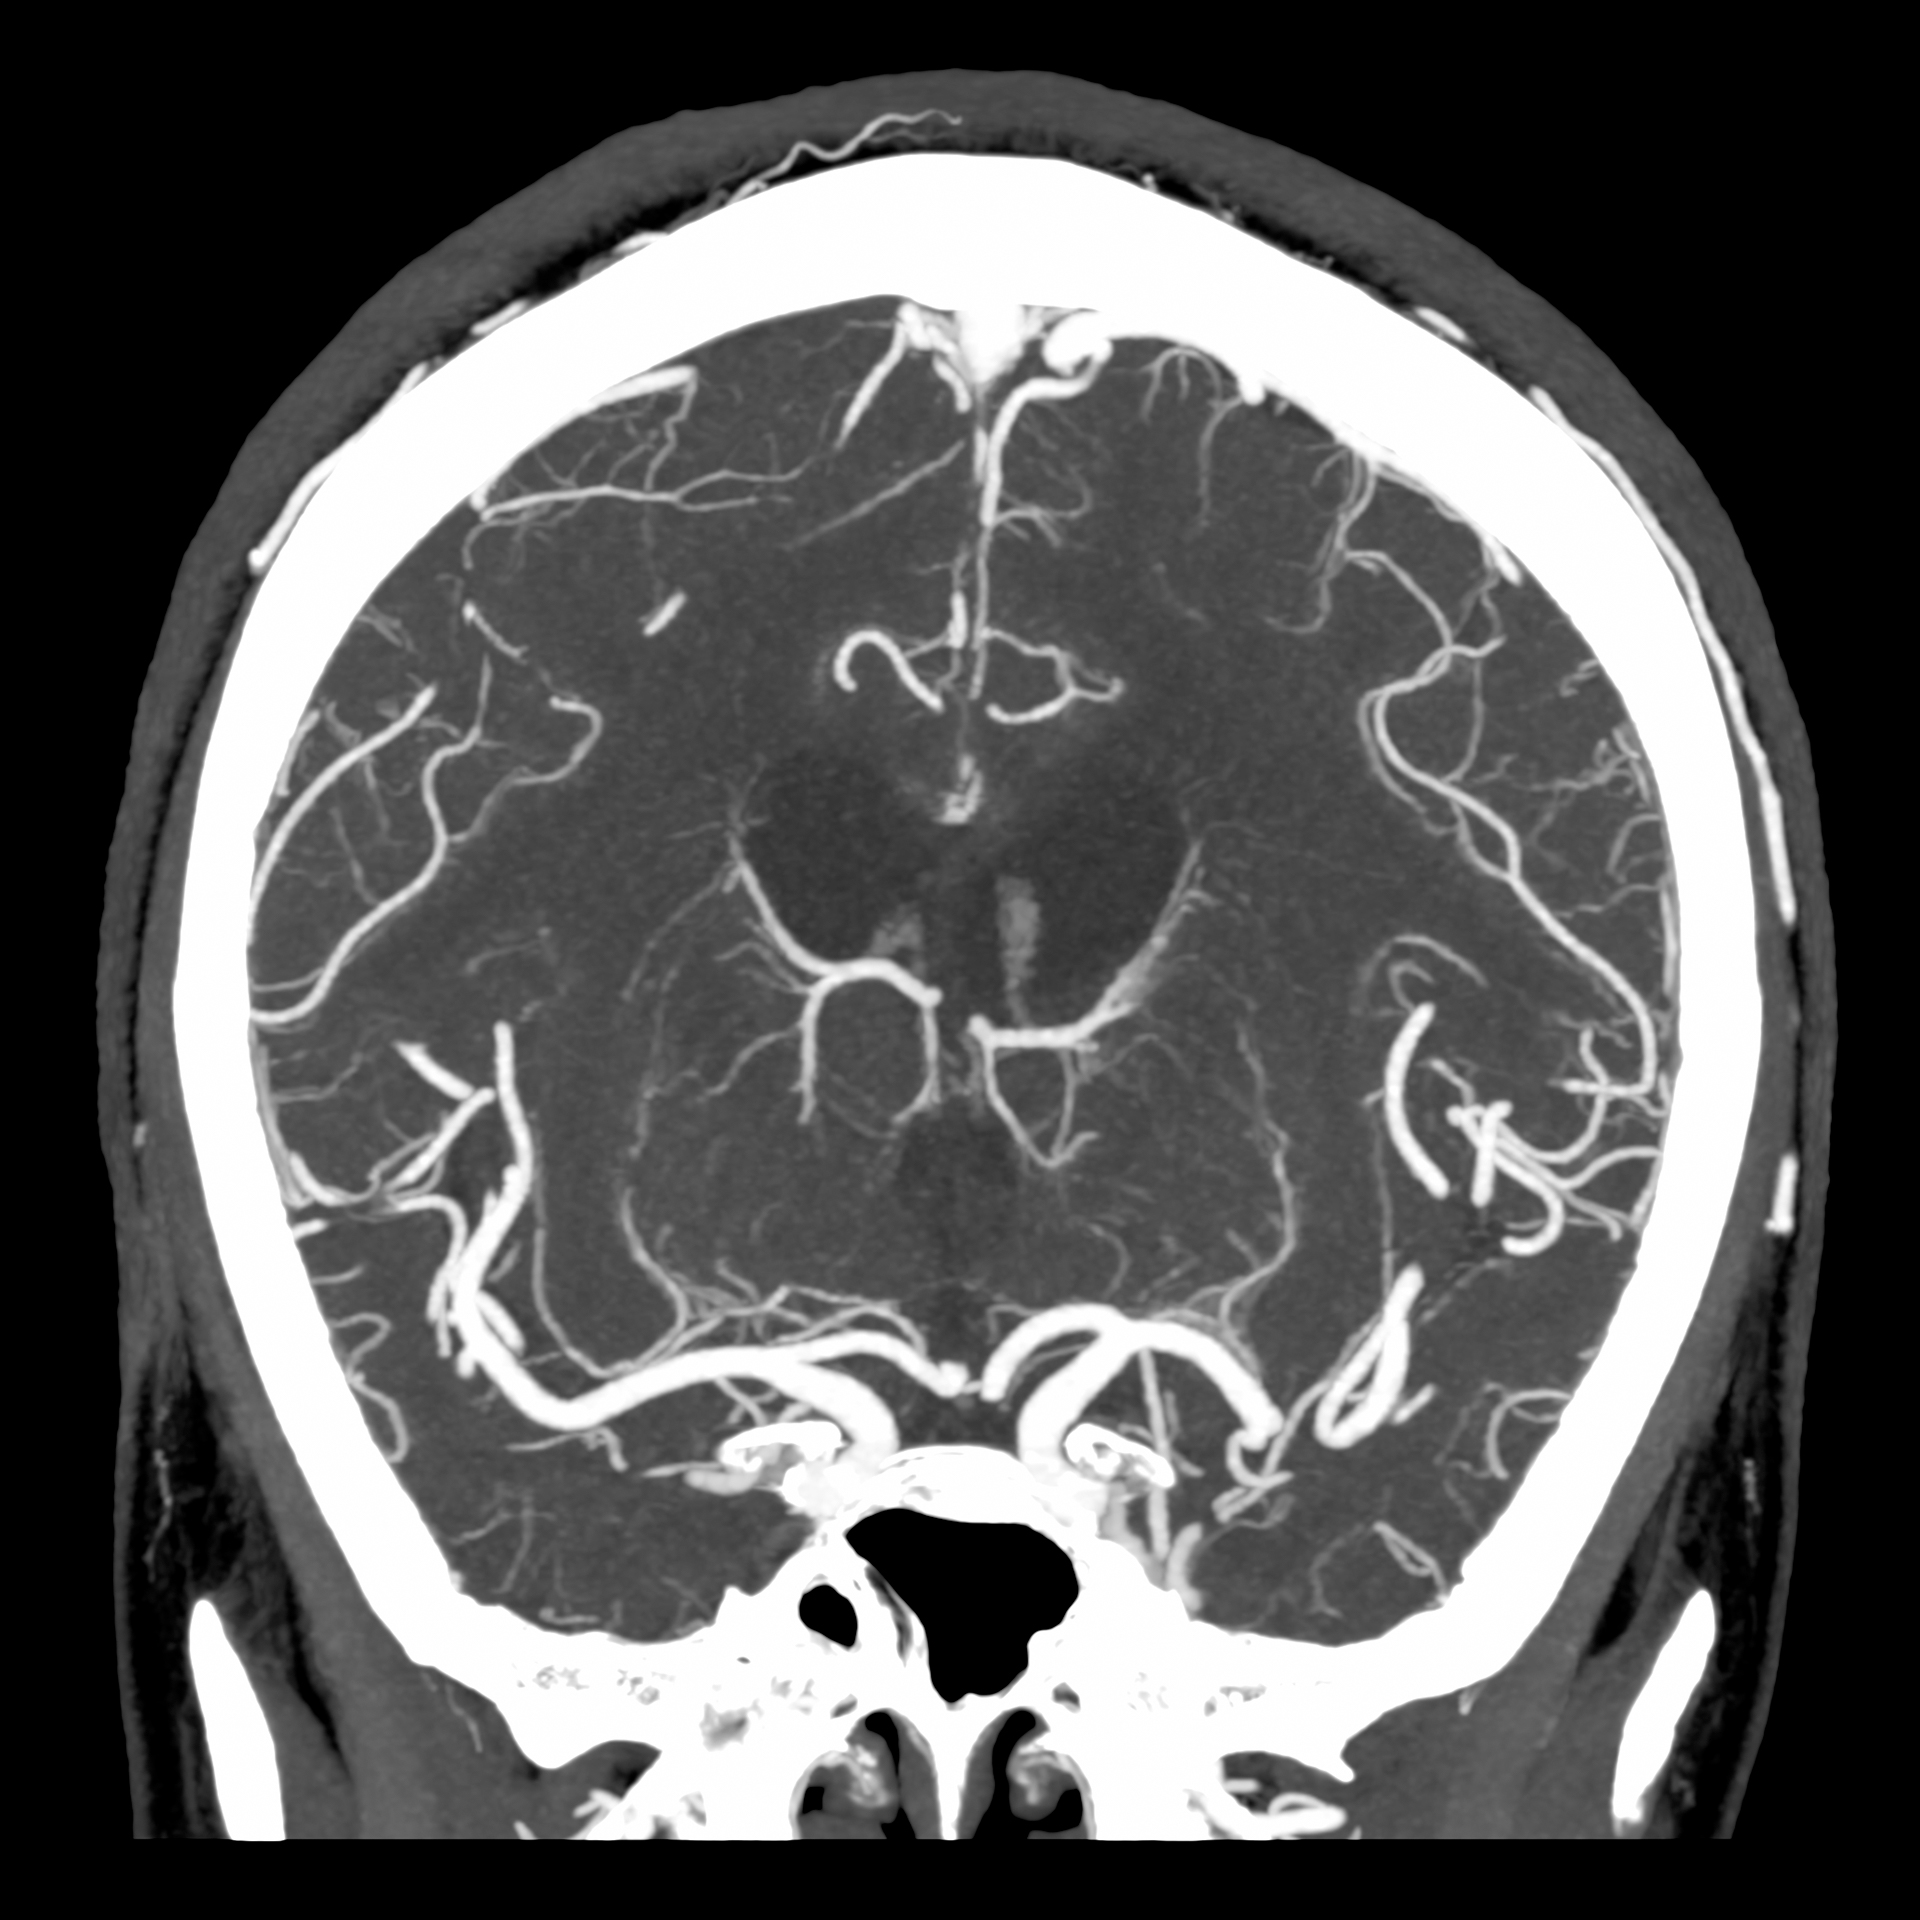

КТ ангіографія голови, 0,25 мм, 1024 матриця¹